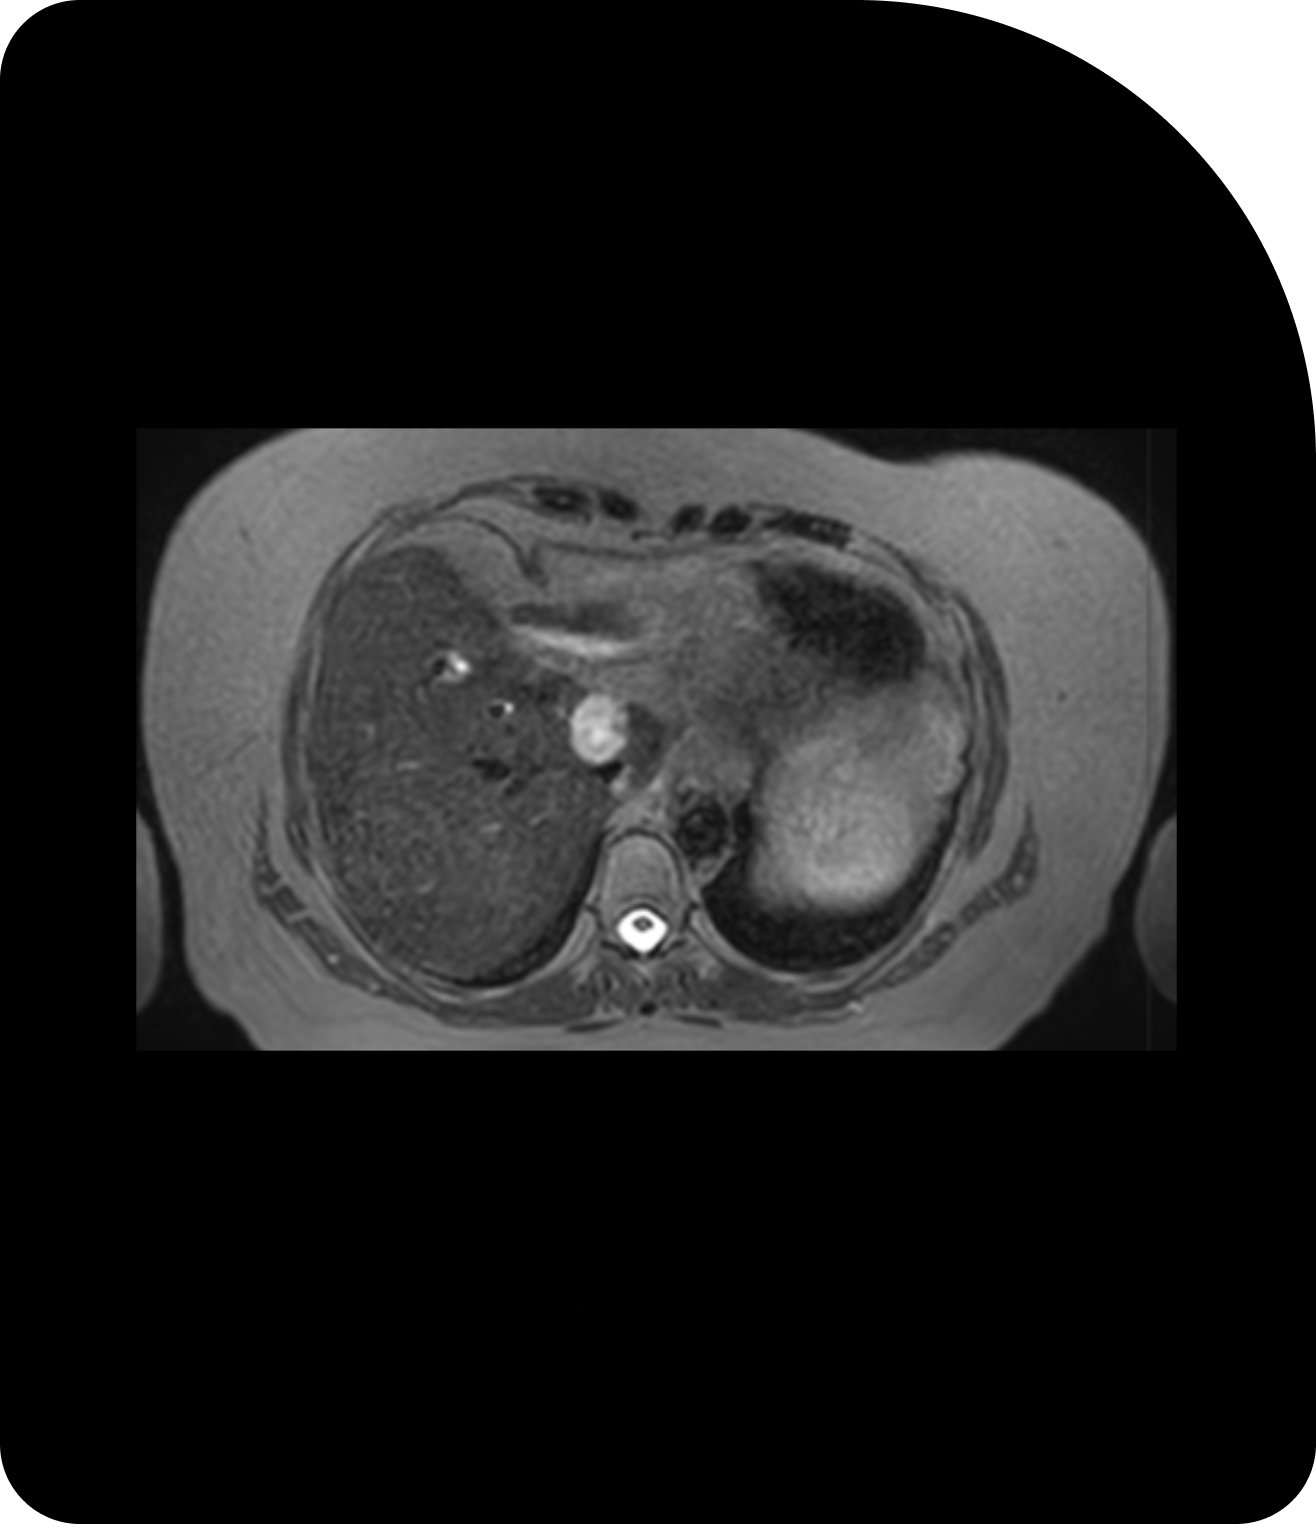

MRI

Superior soft-tissue contrast reveals finer details for precise adaption.

MRI-Guided Radiotherapy

MRI delivers unparalleled soft-tissue contrast, making it especially valuable for tumors near critical organs such as the pancreas, or prostate. MRI also enables real-time imaging during treatment, paving the way for innovations like real-time tracking and gating.